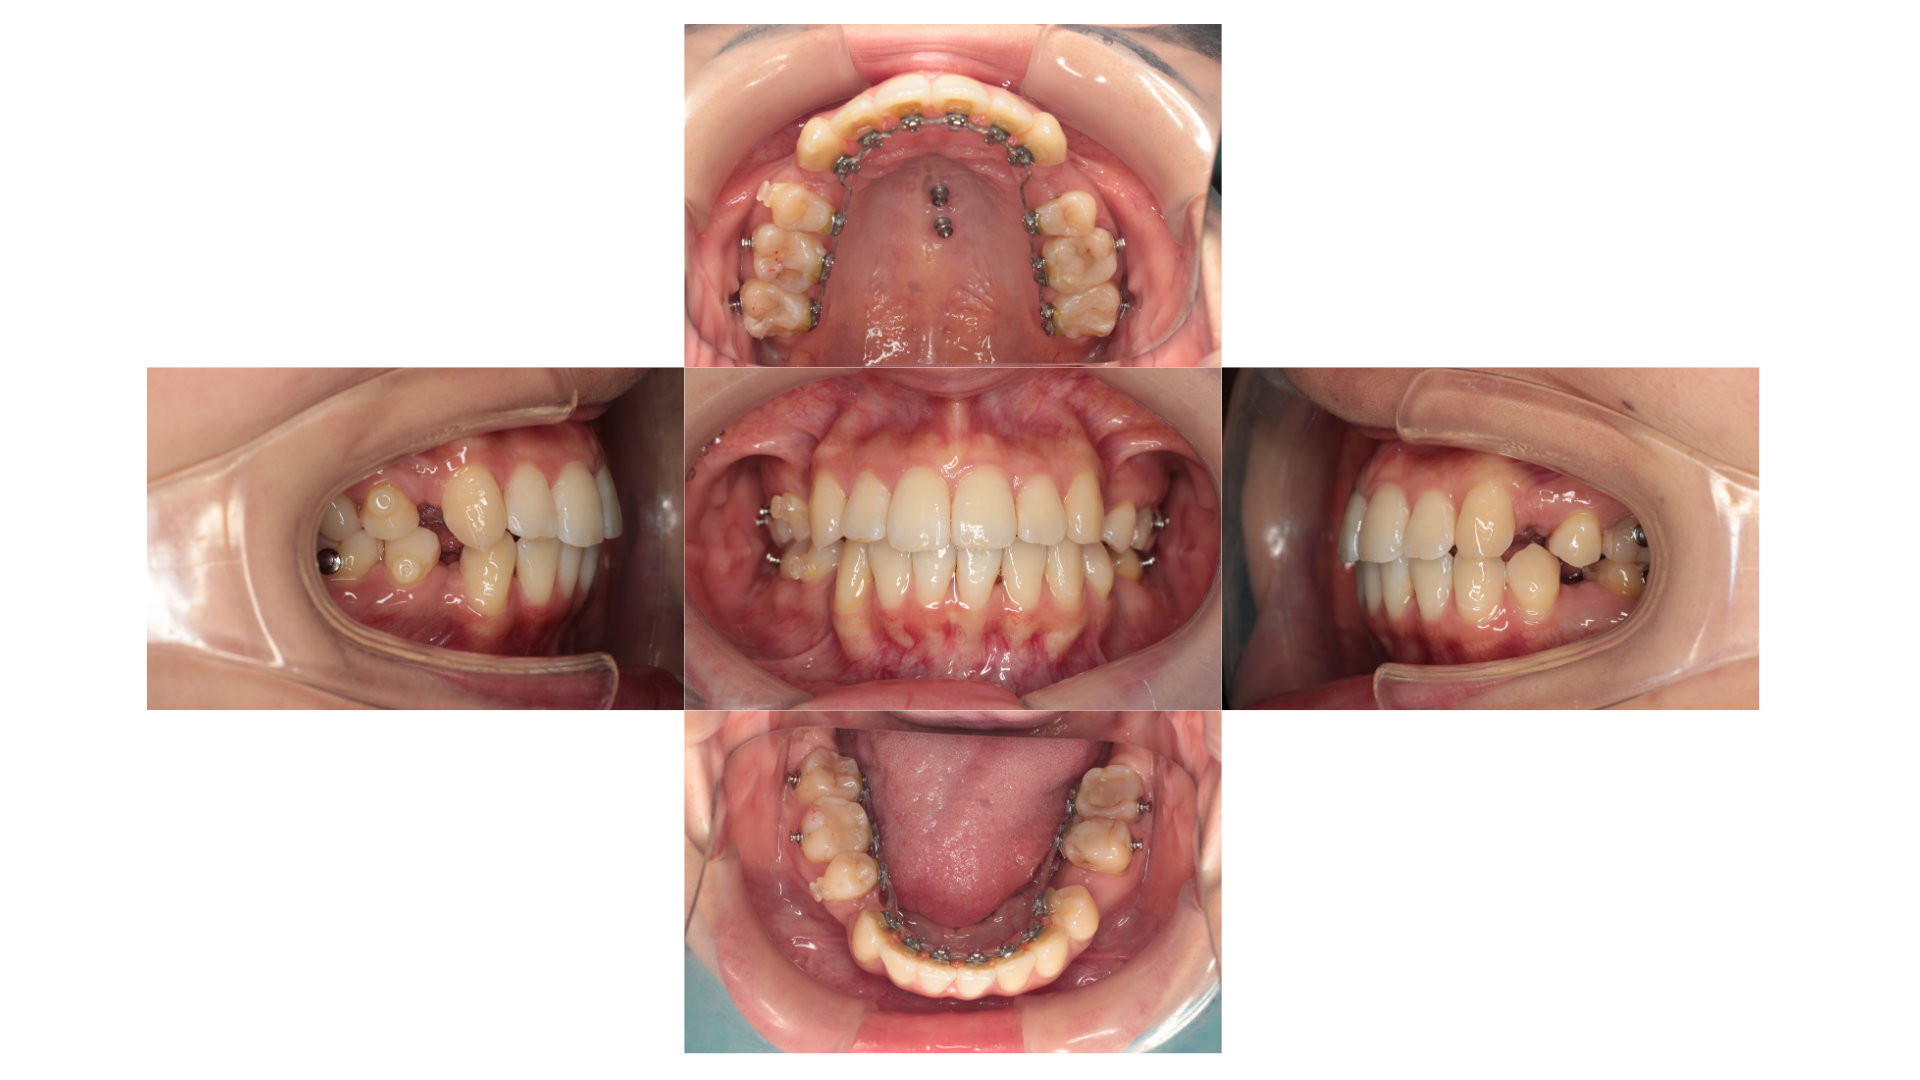

5ヵ月経過時